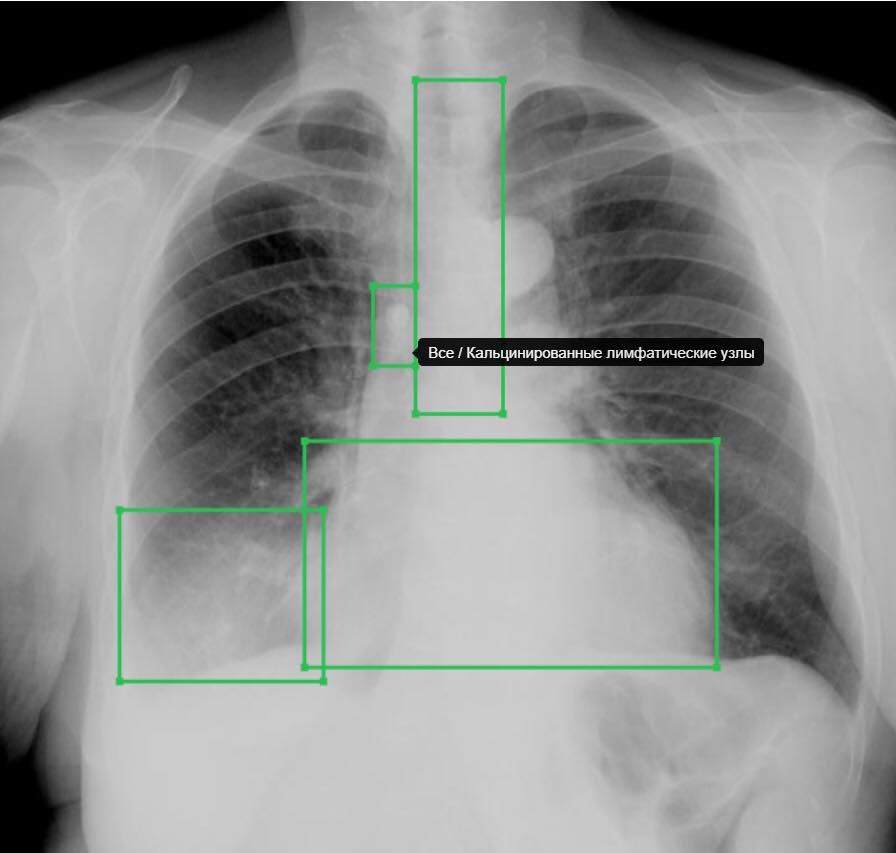

Что значит средостение расширено

Что значит средостение расширено 115 фотографий